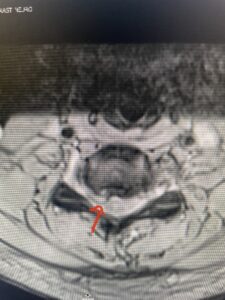

This 47-year-old male who four months prior was lifting weights developed sharp pain in his neck. After that he developed progressive numbness in his arms, neck pain and headache. He said that the right arm was worse than the left. On examination the patient had long tract weakness on the right side which included his triceps, finger extensors, hip flexors, and dorsiflexors. The patient did not have hyperreflexia. MRI (Fig. 2) demonstrated a massive, extruded disc herniation with severe cord compression. The patient because of progressive myelopathy and spinal cord compression was indicated for anterior cervical discectomy and fusion at C4-5 (Fig. 3). Patient had significant improvement of weakness and numbness post operatively.

Fig: 2b Axial T2-weighted cervical MRI demonstrating spinal cord compression from C4-5 herniated disc (red arrow)

Fig 4. Axial T2-weighted MRIs demonstrating large C5-6 herniated disc with spinal cord compression (red arrow)

Fig 4A. Axial T2 weighted MRIs demonstrating large C5-6 herniated disc with spinal cord compression (red-arrow)